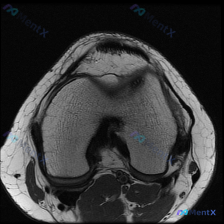

临床提示:怀疑膝关节软骨异常,提供单张膝盖MRI-T1加权轴位图像读片

- 骨骼与骨髓:股骨远端、髌骨皮质完整,无中断;骨髓腔内T1高信号,符合正常脂肪骨髓,没有局灶低信号区

- 关节软骨:股骨滑车面、髌骨后关节面的软骨层完整,信号均匀,没有看到局灶性缺损或者变薄

- 髌股关节:髌骨位置正常,在股骨滑车沟内,没有半脱位,关节间隙清晰

- 其他结构:关节周围脂肪垫等软组织信号正常,没有异常肿胀或占位;也没有看到明显关节腔积液

读片总结:这张单张T1轴位图像上,没有发现明确的结构异常或病理性信号改变,也没有看到支持软骨异常的影像学证据。